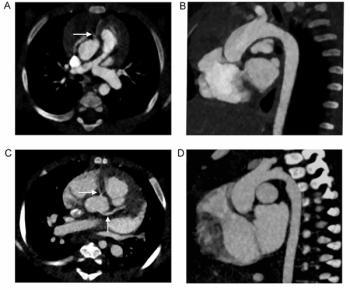

Emphasizing increasing recognition of the capability of coronary computed tomography angiography (CCTA) for the evaluation of acute and stable chest pain, this author defuses common misperceptions and reviews key considerations for implementation of a CCTA program.